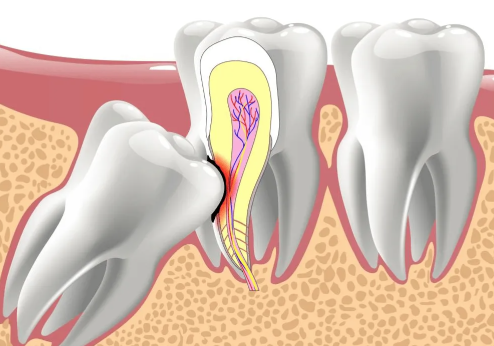

智齿,又称阻生齿或第三大臼齿,通常在16岁以后逐渐萌出。然而,此时牙齿结构已经基本稳定,智齿的出现往往显得“多余”,并可能引发长期疼痛,有时甚至持续三四天。